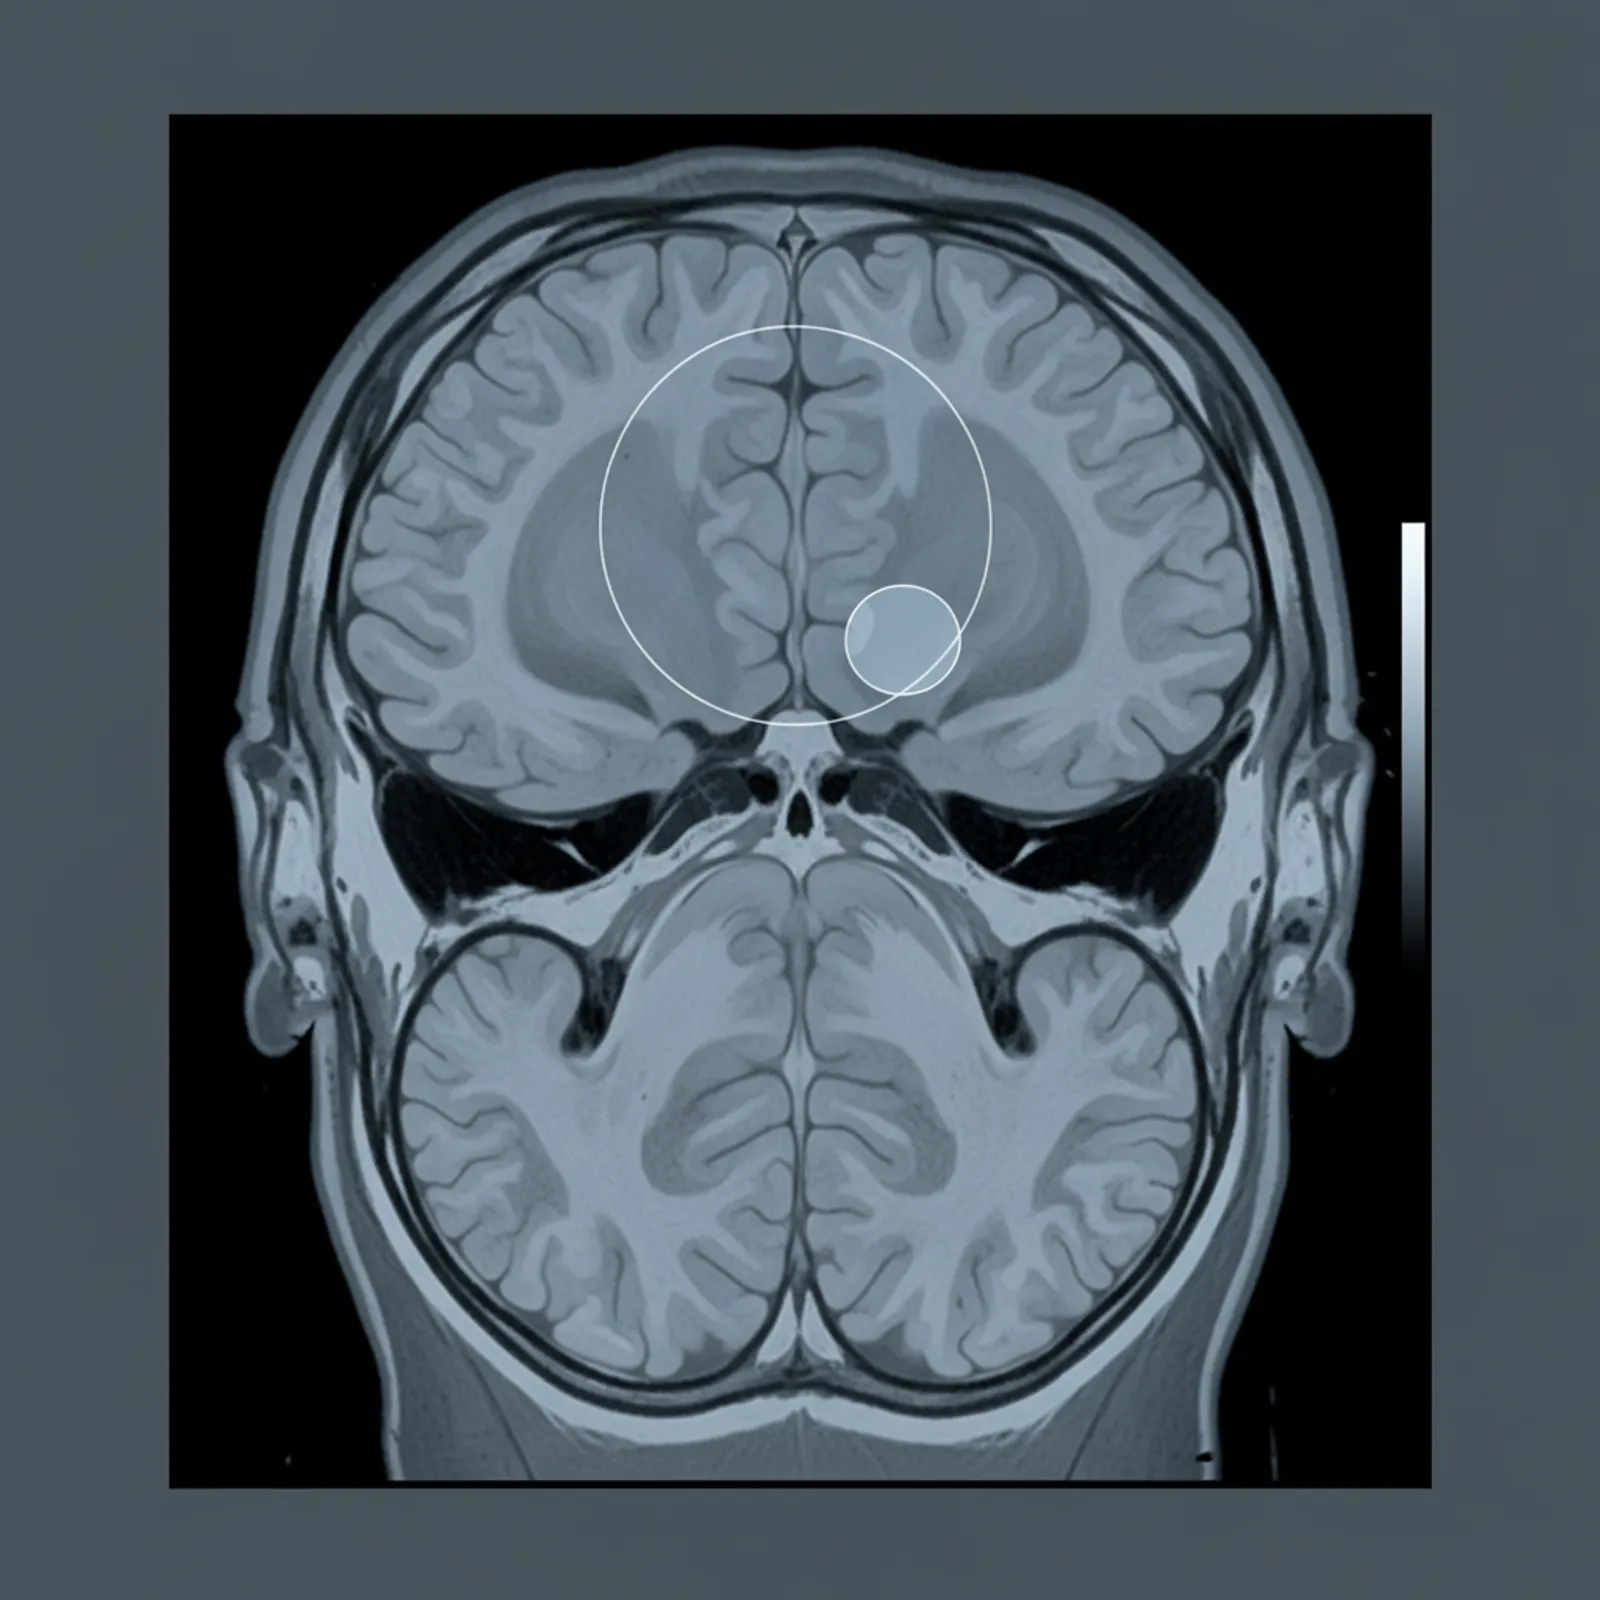

Точная визуализация помогает подобрать безопасный план лечения и снизить риски операции. МРТ остаётся предпочтительным методом при подозрении на фалькс менингиома мрт: он лучше показывает контакт с мозговыми структурами и отёк.

МРТ выявляет размер, распространение и связь опухоли с сосудистыми структурами. КТ полезна при кальцинатах и для оценки кости. Если доступно, делаем контрастирование для уточнения границ. Повторю: фалькс менингиома мрт показывает зоны контраста и отёка.